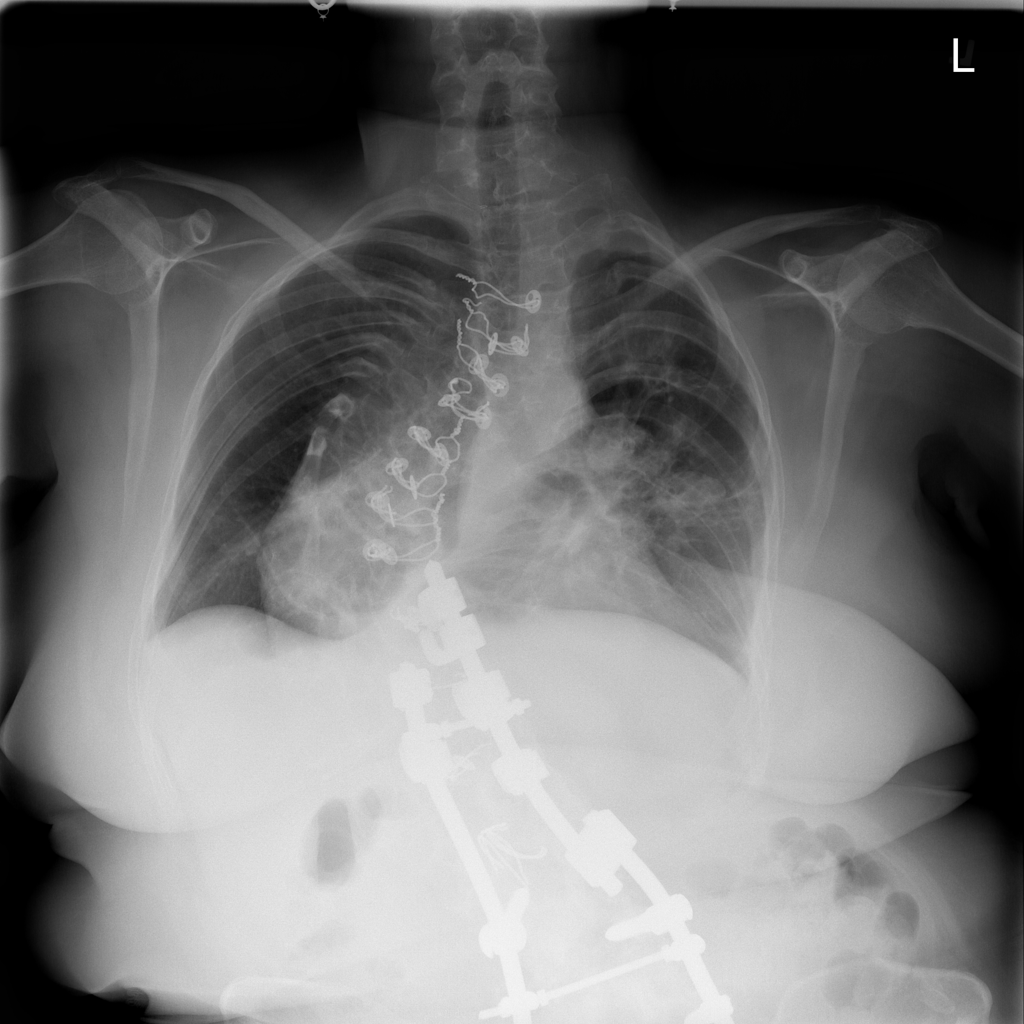

Mass

A mass is a larger focal opacity or lesion seen on the image. It is a descriptive finding that can have several causes and usually needs more imaging or clinical context to characterize.

PAT-D7A5 · IMG-000Mass

PAT-D7A5 · IMG-000

PA